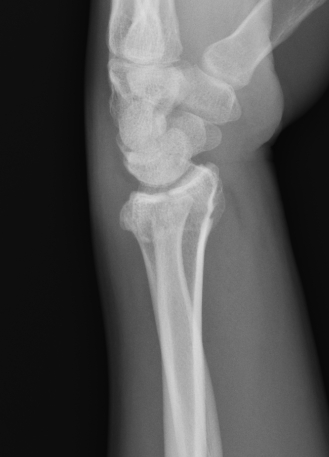

Colle's Fracture

- distal radial fracture with dorsal displacement